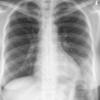

Case 2  Lingular pneum Lat

Date: 04/17/2005

Views: 7429